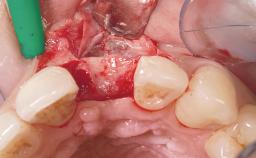

Immediate Flapless Placement of an Implant in a Maxillary Right Lateral Incisor Site

This 43-year-old male patient, a non-smoker, came to our practice because of a fracture of tooth 12 caused by a bicycle accident. Due to the combined para- and infrabony crown and root fracture, tooth extraction, and subsequent implant placement were suggested to the patient as the therapy of choice. The patient had high esthetic expectations with regard to the treatment outcome and asked for an immediate fixed provisional restoration. His individual esthetic risk profile summed up to a medium esthetic risk.

Placement Protocol Immediate implant placement

Tooth Site Maxillary incisor or canine

Socket Morphology Single-root socket

Socket Integrity Sufficient, with intact bone walls

Bone Volume Sufficient, with intact walls